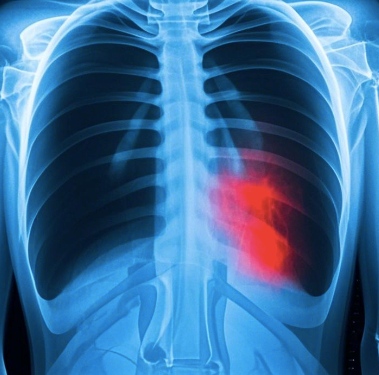

王某某体检时发现胸片结果异常-疑似肺结核,接诊医生督促其到结核病定点医疗机构进一步检查。他心里直犯嘀咕,附近的三甲医院不是更好么?医生为什么要叫我到结核病的定点医疗机构就诊呢?

疑似肺结核,为什么必须到结核病定点医疗机构诊治?

肺结核是我国重点防控的慢性呼吸道传染病,原卫生部颁布的《结核病防治管理办法》中明确规定:结核病定点医疗机构负责肺结核患者的诊断、治疗并落实治疗期间的随访检查。非结核病定点医疗机构接诊结核病患者和疑似患者后,应将其转诊至定点医疗机构。我国省、地、县三级均设有结核病定点医疗结构,结核病门诊和病房的设置均符合《医疗机构管理条例》规定和呼吸道传染病诊疗及防护要求。